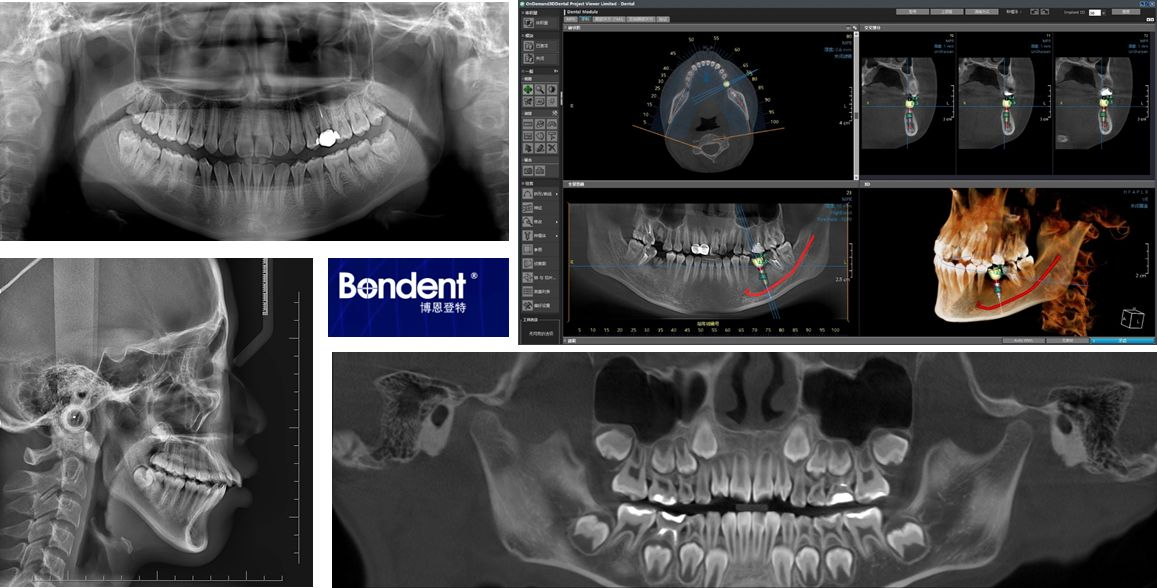

伯爵cbct影像篇⑧拍牙片辐射那些事儿

图片尺寸1157x588